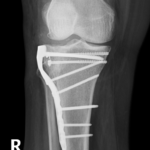

if the fracture is displaced, surgery may be needed to put the bone back into the correct position and fix the bone with Plates & screws or nails for adequate healing to occur.

- Tibial Plateau Fractures.